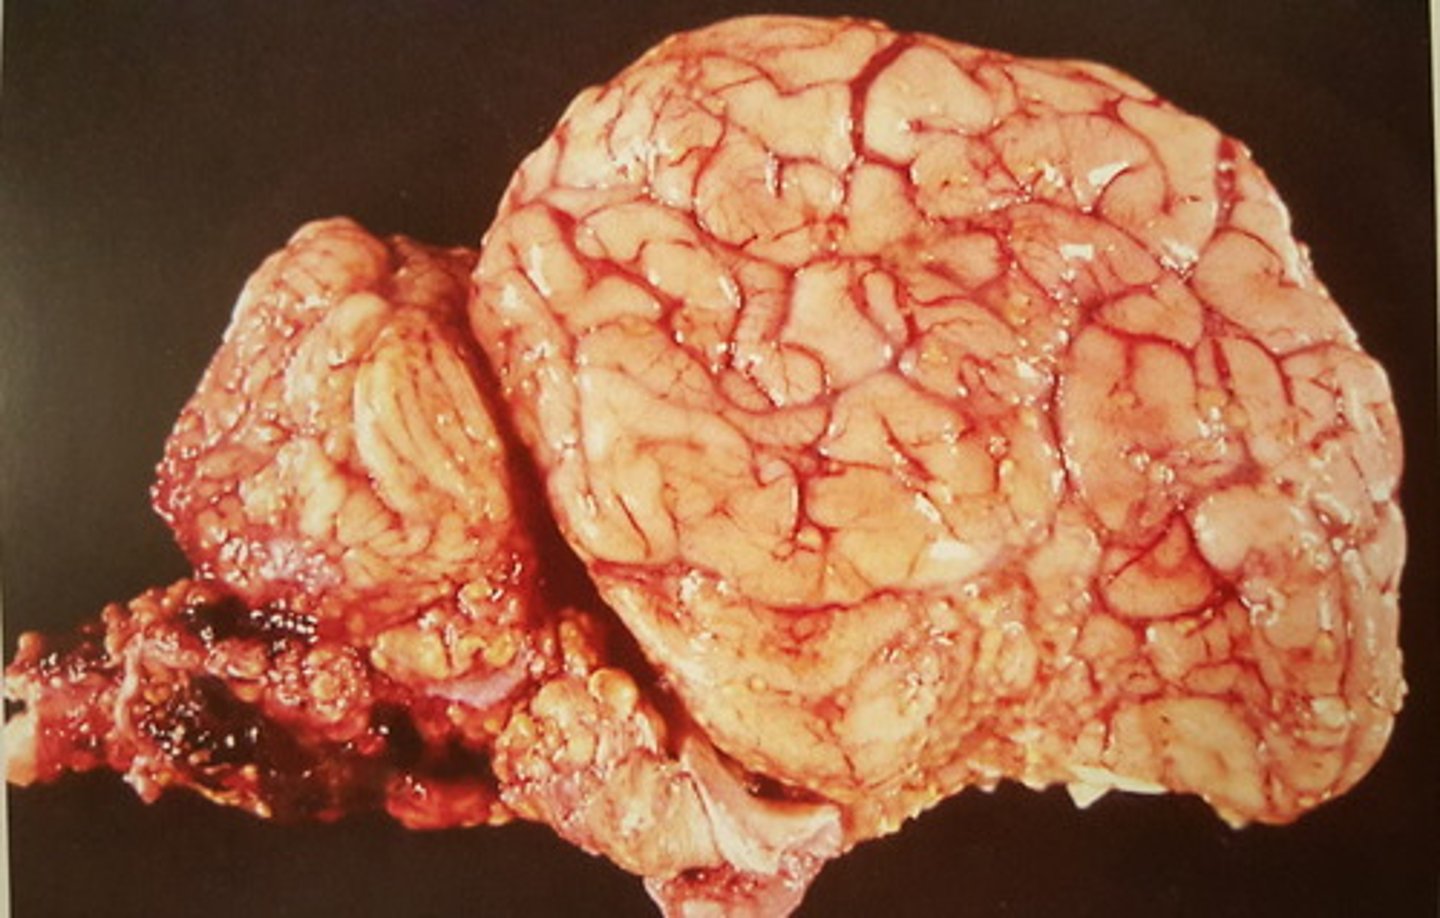

Canalis vertebralis - okse. Patoanatomisk diagnose?

kronisk dissemineret granulomatøs meningitis Infektion med mycobacterium bovis

Rygmarv med hinder fra okse. Patoanatomisk diagnose? Ætiologi?

kronisk dissemineret granulomatøs encephalitis og meningitis. Infektion med mycobacterium bovis

Hjerne med hinde fra okse. Patoanatomisk diagnose? Ætiologi?

udbredt forekomst af Schwannomer

Perifere nervesystem hos okse. Patoanatomisk diagnose?

multiple Schwannomer

Intercostalnerver hos okse. Patoanatomisk diagnose?

R=ribben, N=nerver, I=muskulatur